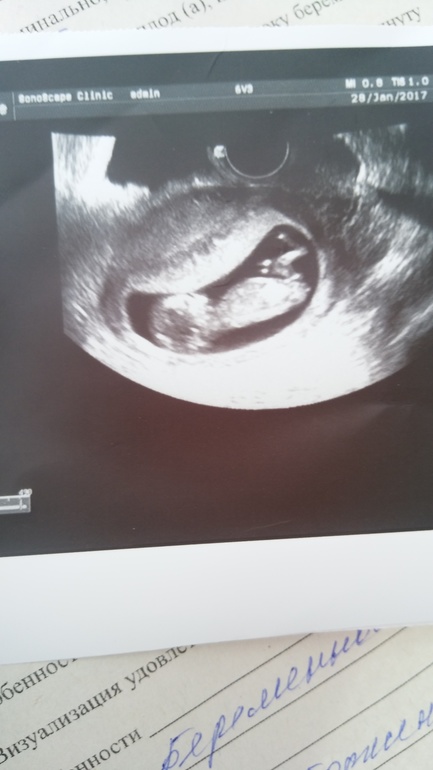

Наконец то дождалась 1 скрининг,врач сказала все нормально ждем рез-т крови .но что то мне кажется что на голову как будто давит .Или я накручиваб себя ?!

А по-моему, на снимке тонус у вас. Может, переживали перед УЗИ, вот и появился. Хотя, может и место прикрепления плаценты так отобразилось. Врач ничего не сказал?)

Зато малышик четко показался.) Поздравляю вас с хорошими новостями.)

Я первый раз когда увидела тоже подумала, Боже ей там так тесно и плаценту прям на лицо давит, но на самом дела места им там пока предостаточно так что не переживайте )